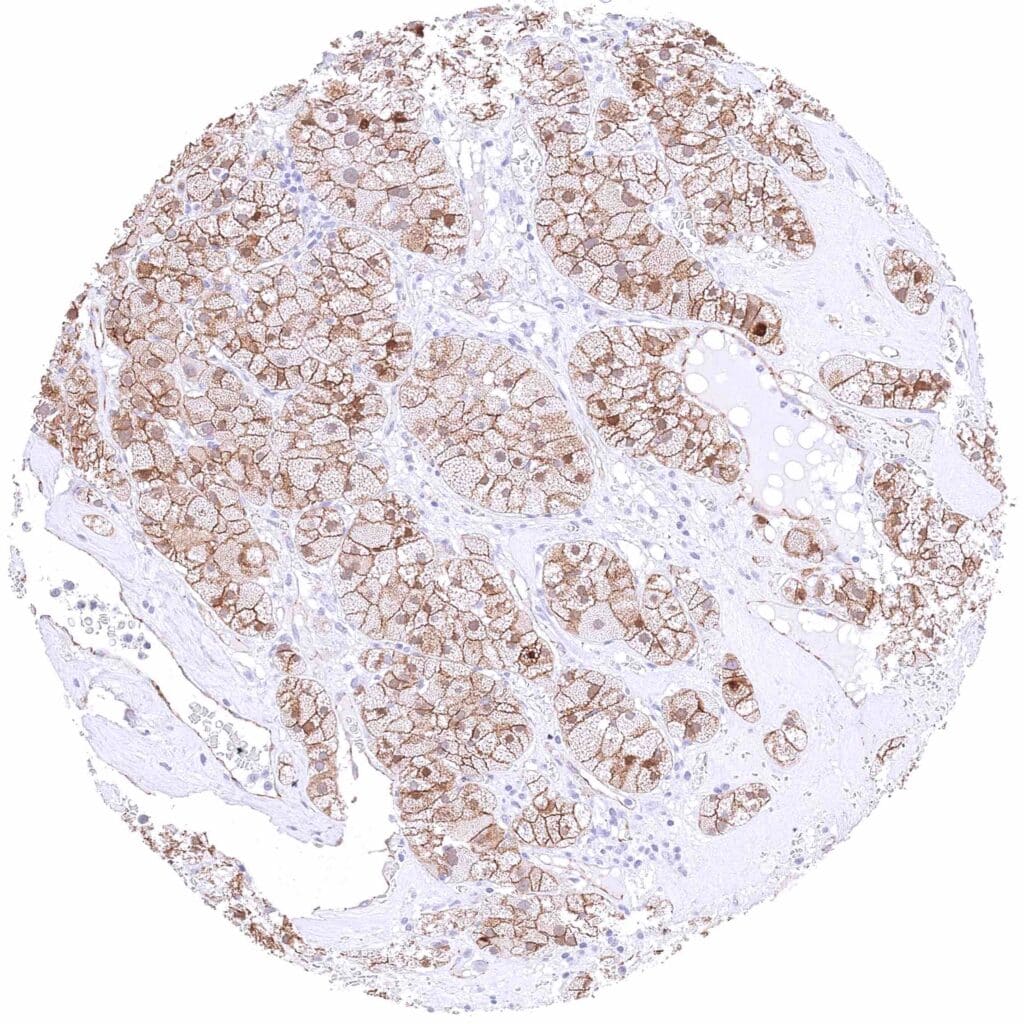

Pancreas – Neuroendocrine tumor with weak membranous, moderate cytoplasmic, and strong nuclear β-Catenin staining of tumor cells.